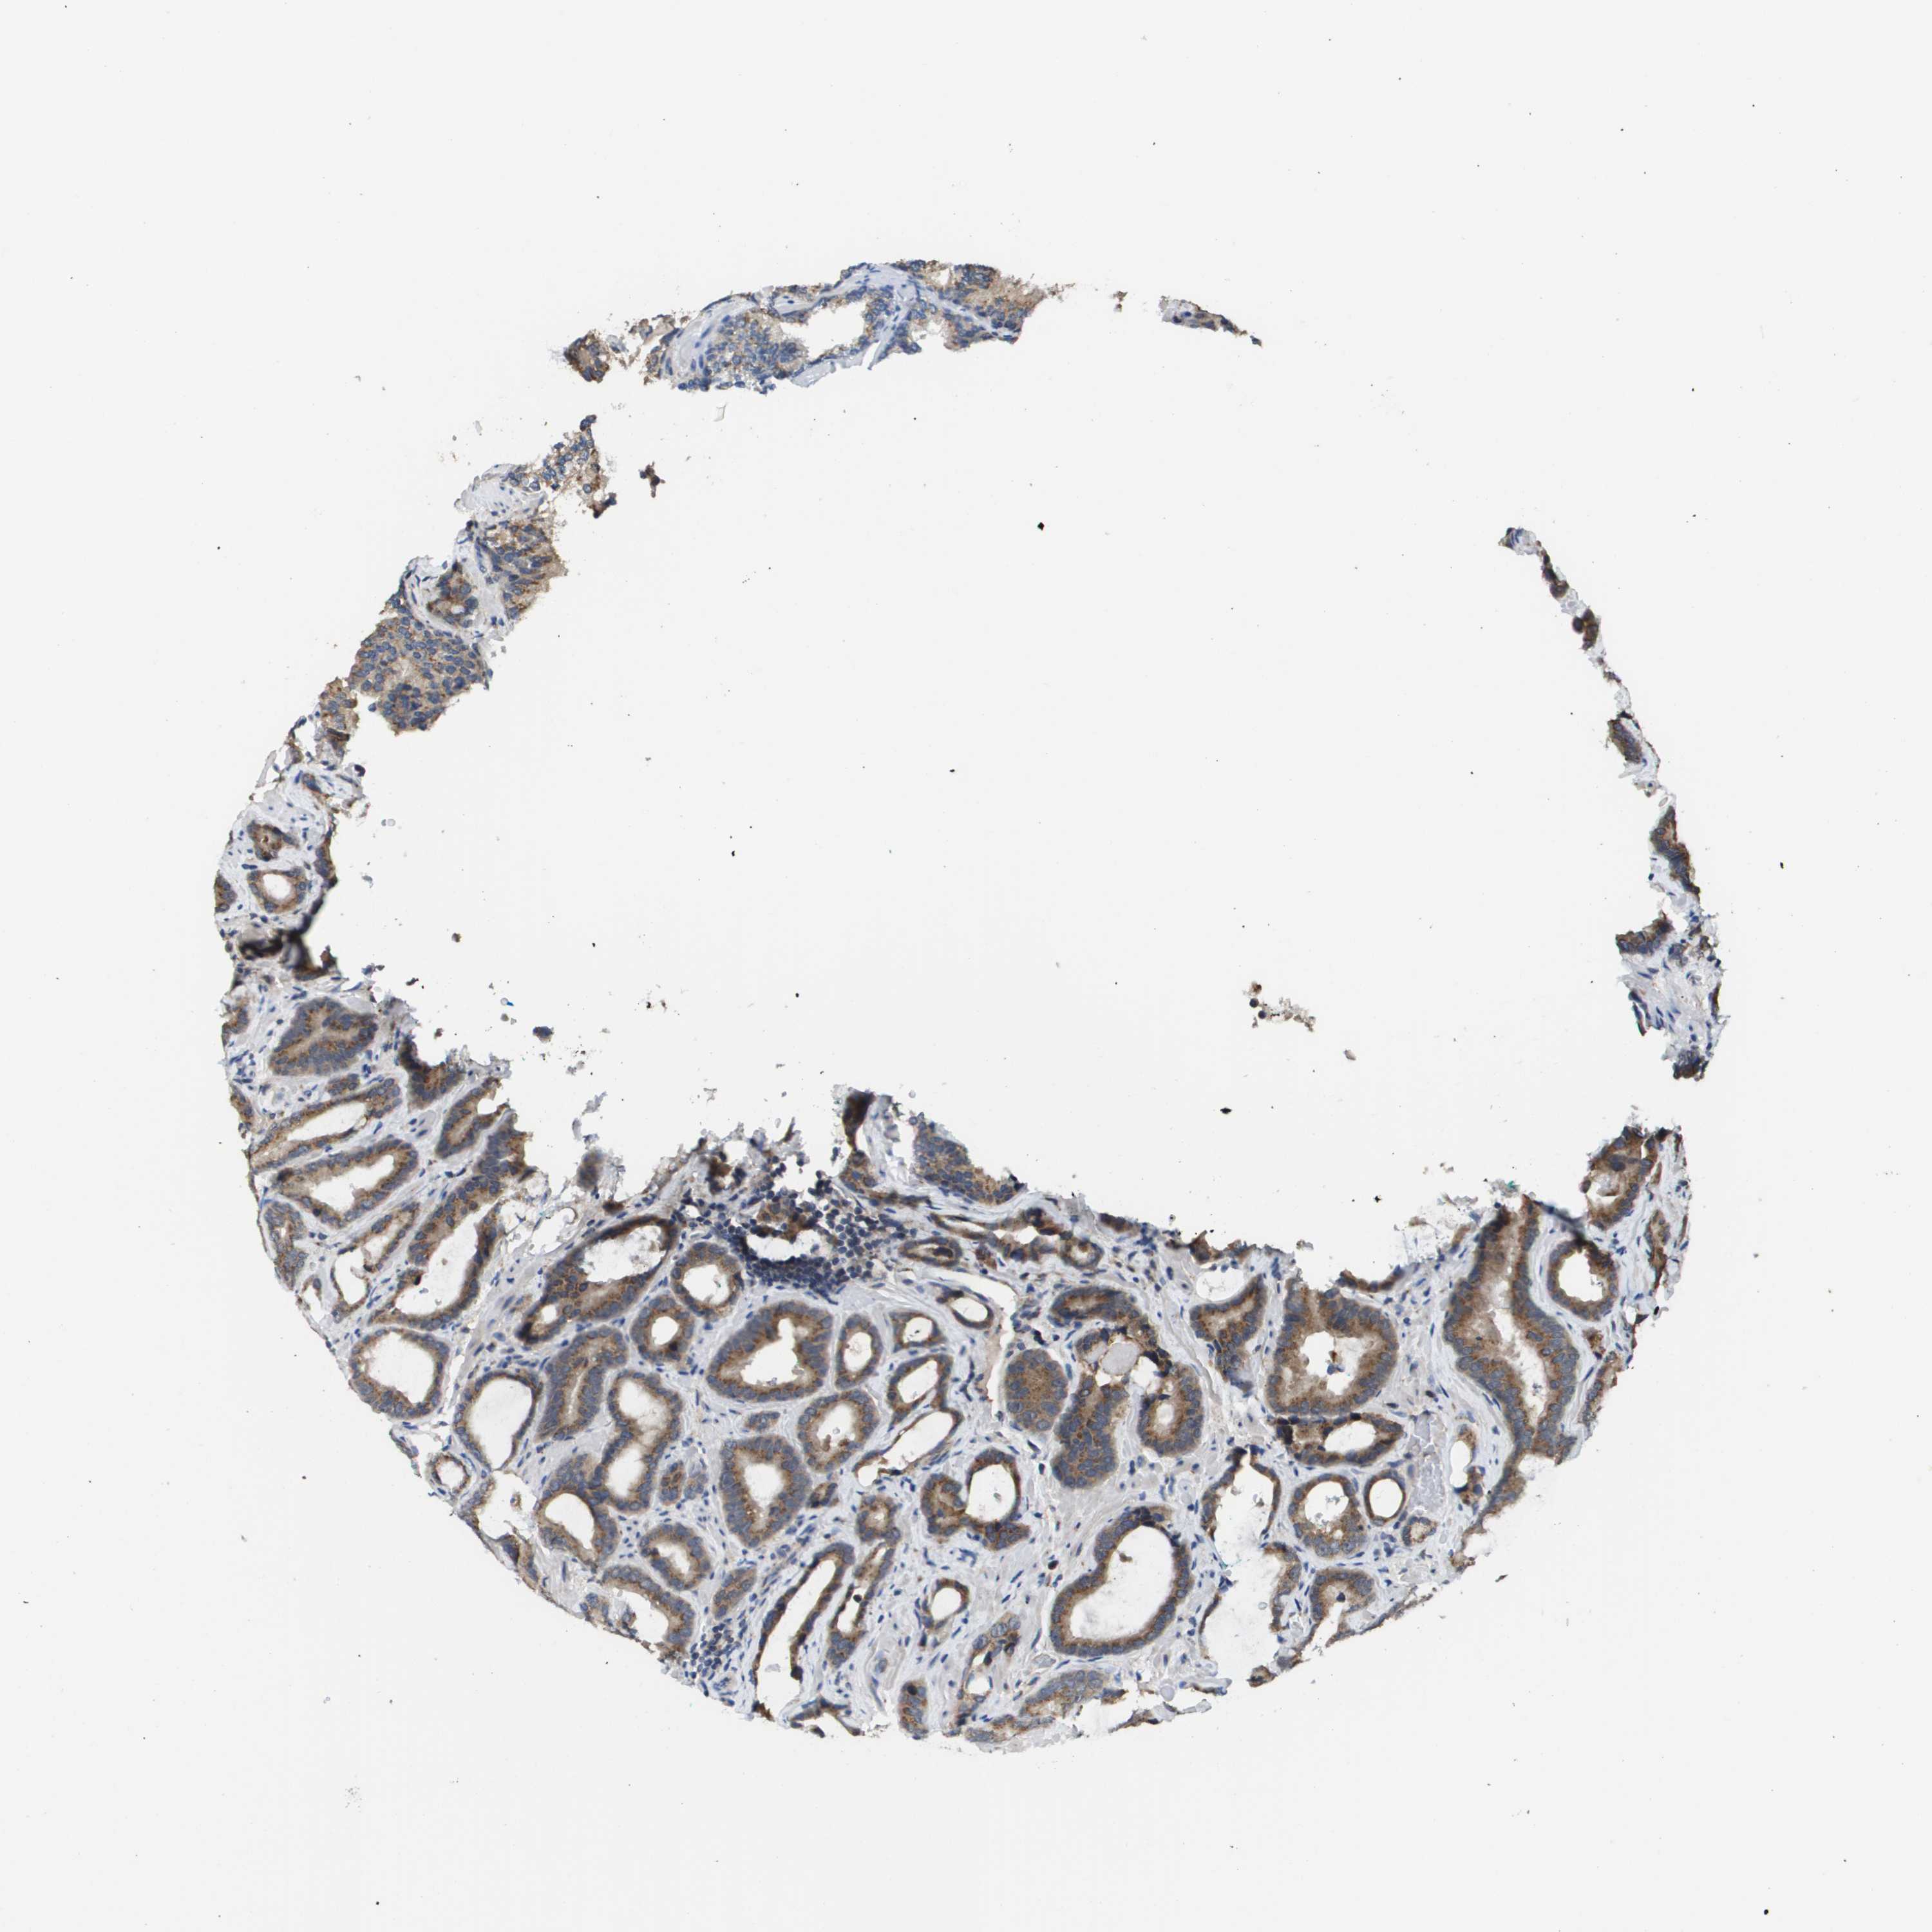

PROSTATE CANCER - Protein expressioni

A mouse-over function shows sample information and annotation data. Click on an image to view it in a full screen mode. Samples can be filtered based on level of antibody staining by selecting one or several of the following categories: high, medium, low and not detected. The assay and annotation is described here.

Antibody stainingi

Antibody staining in the annotated cell types in the current human tissue is reported as not detected, low, medium, or high, based on conventional immunohistochemistry profiling in selected tissues. This score is based on the combination of the staining intensity and fraction of stained cells.

Each image is clickable and will lead to virtual microscopy that enables deeper exploration of all samples and also displays staining intensity scores, fraction scores and subcellular localization as well as patient and tissue information for each sample.

Antibody HPA006277

Antibody HPA006507

Antibody CAB017027

Staining

High

Medium

Low

Not detected

Intensity

Strong

Moderate

Weak

Negative

Quantity

>75%

75%-25%

<25%

None

Location

Nuclear

Cytoplasmic/membranous

Cytoplasmic/membranous,nuclear

Adenocarcinoma, High grade

Adenocarcinoma, Low grade